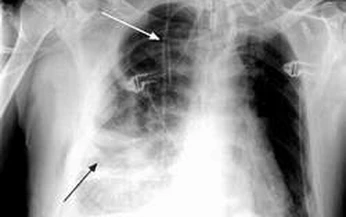

Viêm mủ màng phổi là tình trạng viêm tràn mủ trong khoang màng phổi. Bệnh diễn tiến cấp tính, bán cấp và mạn tính, gây tổn thương màng phổi toàn thể hay khu trú. Mầm bệnh có thể là vi khuẩn thường, trực khuẩn lao hoặc ký sinh trùng như amip...

Viêm mủ màng phổi (VMMP) là sự tràn mủ trong khoang màng phổi. Dịch là mủ thật sự hoặc là chất dịch đục hay màu nâu, nhưng bao giờ cũng có xác bạch cầu đa nhân là thành phần chính của mủ.